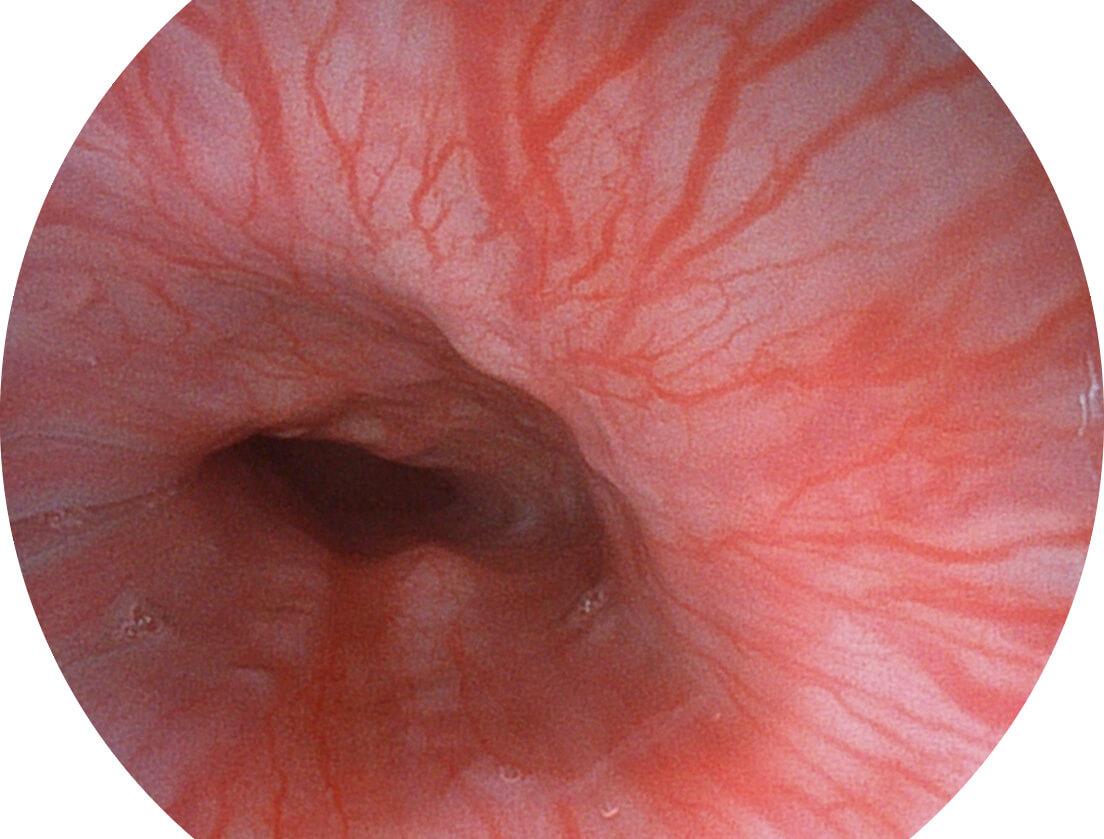

Versatile Intelligent Staining Technology, VIST

强调浅层黏膜结构的同时,保证照明亮度和提升浅层微血管与中层血管颜色对比度,病变边界更清晰。

白光图像

VIST图像